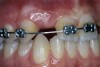

Periapical radiographs were taken to help determine the mesial-distal inclinations of the adjacent tooth roots (Figure 1). The radiographs revealed a serious issue, convergent roots for the right canine and right central, which eliminated that area as a potential implant-receptor site. The space between the left central and canine teeth was minimal, although the roots were relatively parallel. Clinical examination (manual palpation of the root eminences superiorly to the vestibule on the right side) confirmed the root convergence (Figure 2A). The flat, wide zone of the keratinized tissue and lack of interdental papilla was evident for the missing right lateral incisor. There was a marked difference in clinical appearance for the left lateral, which could impact the eventual plan of treatment (Figure 2B). Other significant clinical findings included bilateral facial bone concavities, which existed as a result of the congenitally missing tooth roots. As a diagnostic cue to the underlying bone topography, it is important to follow the demarcation between attached and unattached gingival tissue, and note the crestal width of the available keratinized tissue (Figure 2C).

Figure 2a  Pretreatment buccal views showed (A) root convergence, (B) a difference in clinical appearance of the left lateral, and (C) significant crestal width of keratinized tissue.

Figure 2a

Figure 2b  Pretreatment buccal views showed (A) root convergence, (B) a difference in clinical appearance of the left lateral, and (C) significant crestal width of keratinized tissue.

Figure 2b